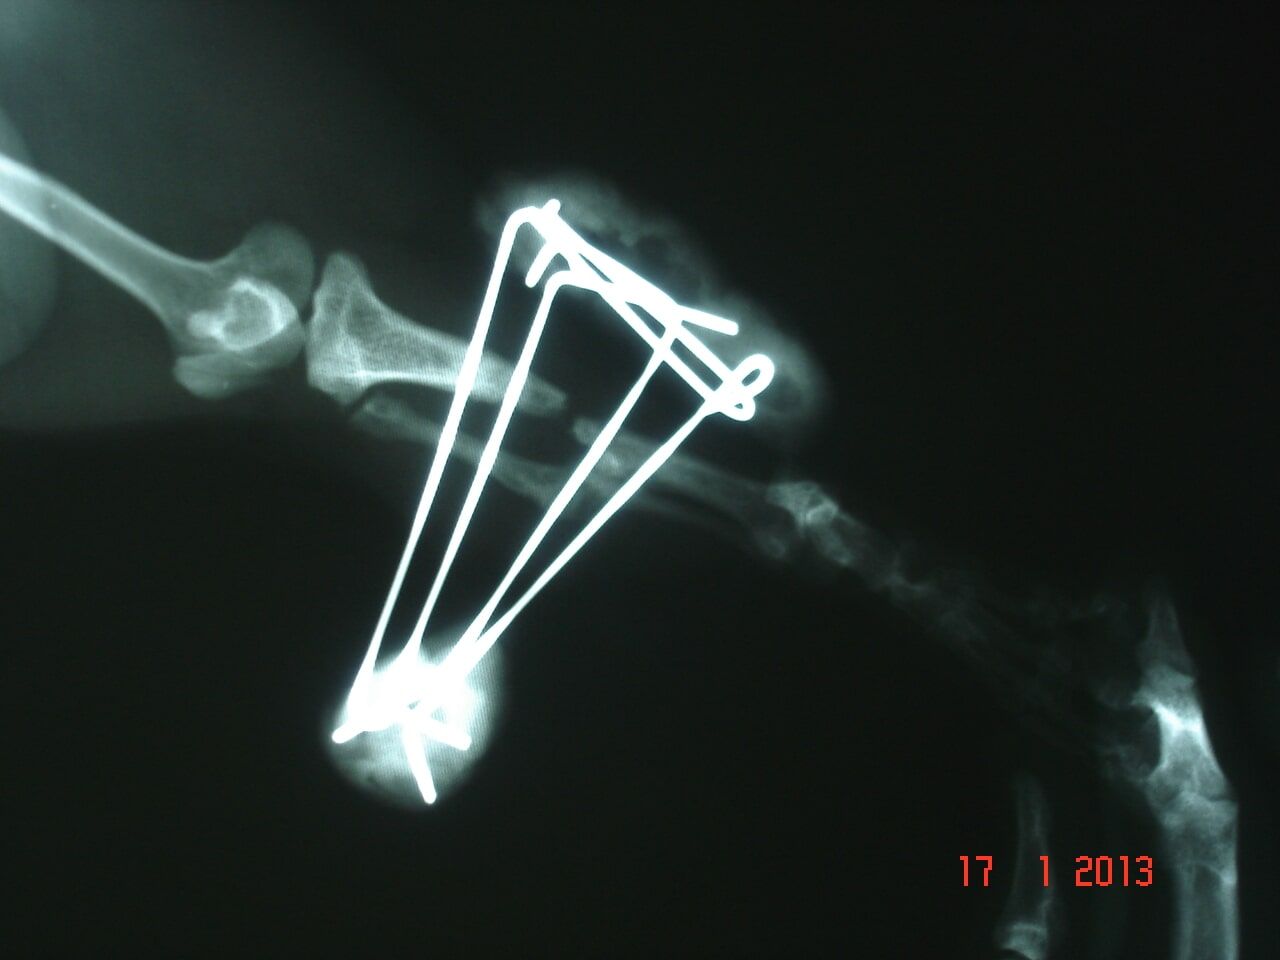

Χειρουργικές επεμβάσεις σκληρών μορίων (ενδεικτικά: κατάγματα, εξωτερική οστεοσύνθεση , ρήξη χιαστών, εξάρθρημα επιγονατίδας)